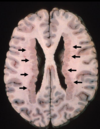

Multiple Sclerosis

Periventricular plaques